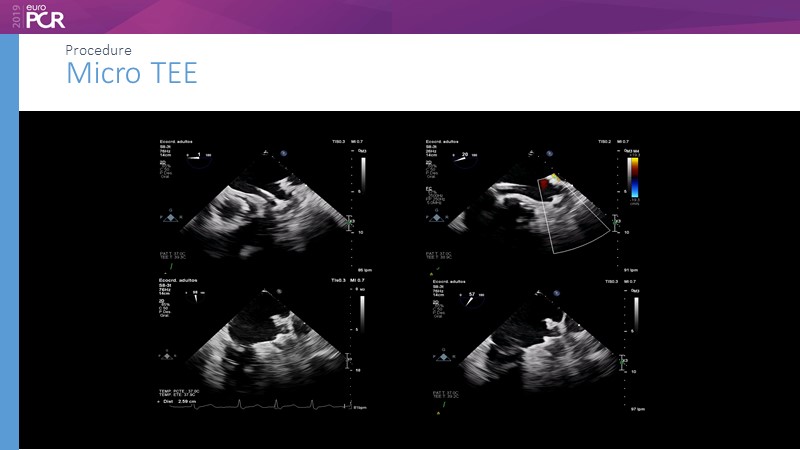

Optimising procedural outcome and safety

Previous Next